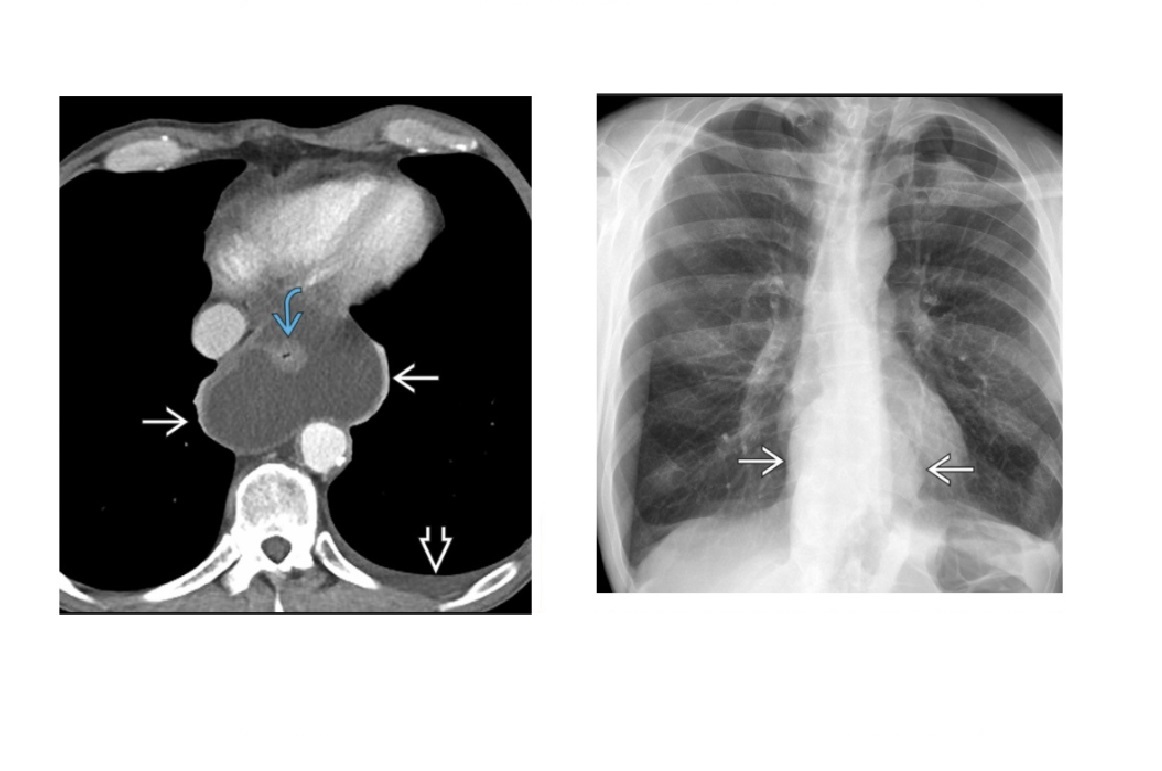

Sigmoid Vovulus Inverted U shape Ahaustra Coffee bean - cleft is double thickenss of opposed bowel loops Directed toward right upper quadrant (RUQ) or left upper quadrant (LUQ); Look for - Gas in proximal small bowel and colon Abscence of air in rectum Tend to be older patients Mx with rectal decompression

60